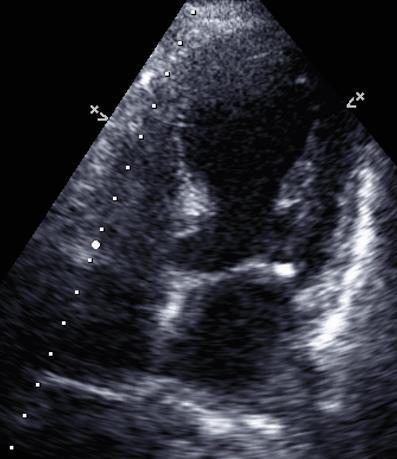

IDENTIFICATION OF AN OPTIMAL METHOD FOR ECHOCARDIOGRAPHIC RIGHT VENTRICULAR MASS ESTIMATION IN A SWINE MODEL OF PULMONARY HYPERTENSION

Jonas Marx1 , Tomoki Sakata2, Renata Mazurek2, Anjali Ravichandran2 , Spyros

Mavropoulos2 , Taro Kariya2, Kiyotake Ishikawa2

1Mount Sinai Morningside-West Hospitals, Icahn School of Medicine at Mount Sinai, New York, NY, United States;

2Mount Sinai Hospital, Icahn School of Medicine at Mount Sinai, New York, NY, United States

To be presented at the American Society of Echocardiography Annual Scientific Sessions that will be held in National Harbor, Maryland, United States from June 23-26, 2023. 45